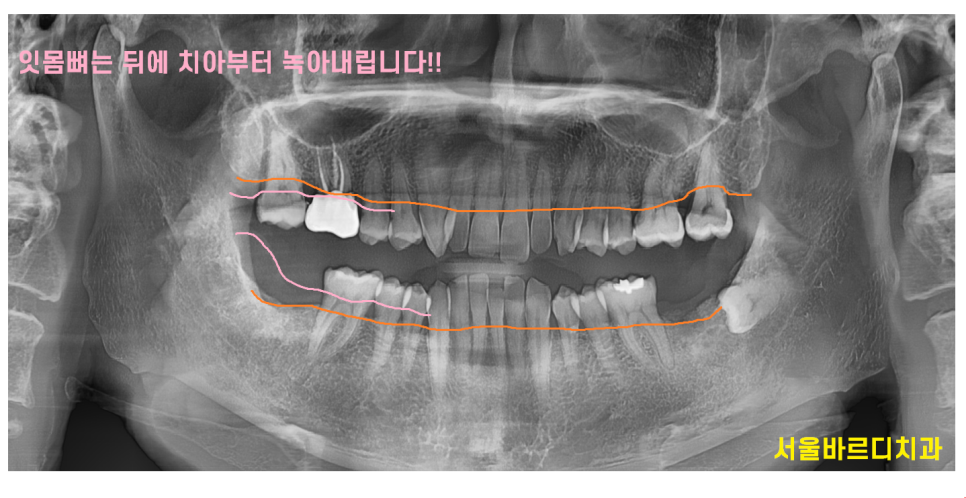

잇몸은 한번 손상을 받으면 회복이 어렵다!!

치주염은 잇몸과 주변 조직까지

영향을 끼친다 설명을 드렸죠~?

뼈가 녹기때문에

치주염 상태에서 고덕동 치과를 방문하시면

녹은 뼈를 재생시킬 수는 없습니다.